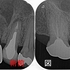

メタルアンレーが割れる!?

個人的に非常に珍しいケースなのですが、

患者さんから連絡があり、「奥の銀歯がかけた」とのこと

これだけ聞くと銀歯の周りの歯がかけたかかな!?と思っていたのですが、

実際口の中を診させてもらうと

2026EEdental KOM (1).jpg

一番したの奥歯インレーの一部が割れて無くなっている・・・

個人的に患者さんにはクリアランス(隙間)が少ないような場合、

「金属は1mm程度厚みがあれば割れない」とゴールドクラウンなどの説明しているんですが、金属が割れている。。。

金属断面を顕微鏡で観察していると、もしかして鬆が入っていたのかも!?

機能咬頭側の金属が割れていますが、そろそろ止めませんか!?この便宜形態

鋳造精度がよければわざわざ裂溝削る必要などないと思うのですが・・・

虫歯1に対して、健康な部分を3~5を削り犠牲にする方法がこのインレー

大学で教えられるブラックの窩洞という基準ですが、これって1908年でかれこれ120年前の明治時代の治療基準を令和になっても未だに採用って。。。

経験上、メーカーの開発で接着技術が格段に向上した1990年移行

コンタクトカリエスの99%はレジン治療で大きく削らず治療出来る時代です。

*歯科医師技術は多少必要です。

患者さんにはこれだけ健康な歯が残っていれば、金属でなくレジンでも大丈夫と説明しレジン充填させてもらいました。

2026EEdental KOM (2).jpg

術後(治療時間1時間)